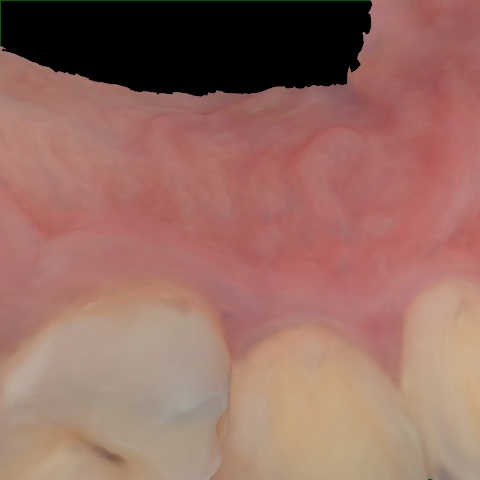

Annotated as "Good"